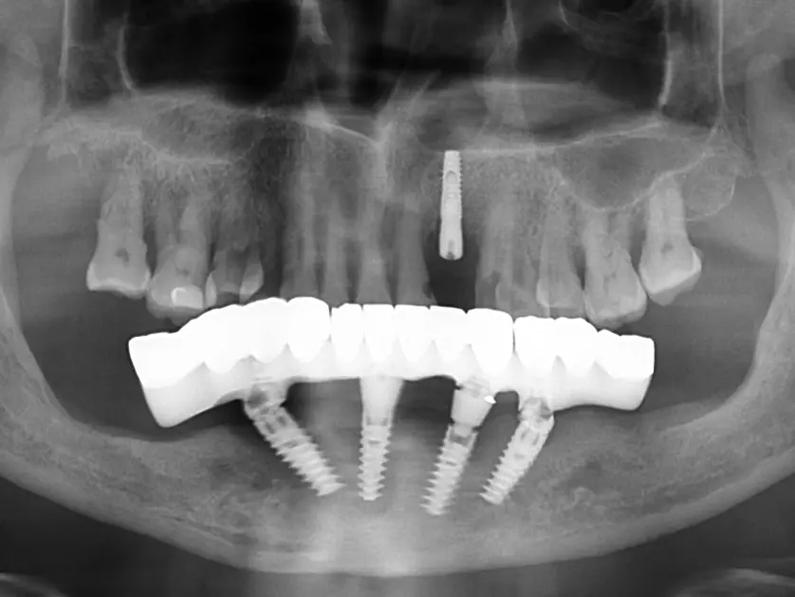

在硬件设施方面,医院引进了德国卡瓦CBCT影像系统、意大利NewTom口腔扫描仪等先进设备,实现了从诊断到治疗的全流程数字化管理。特别是在种植牙领域,采用计算机导航种植技术,将种植精度提升至0.1mm级别。

- 即刻种植技术:实现当天拔牙、当天种植、当天戴牙的快速修复

- 全口种植修复:为缺牙患者提供功能性与美观性兼备的解决方案